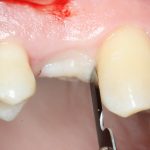

Затем рана скелетируется, открывается кость верхней челюсти:

Поскольку ранее мы сделали и внимательно изучили компьютерную томографию, то для нас никаких неожиданностей на этом этапе нет и быть не может. Мы спокойно приступаем к подготовке лунки под имплантат.